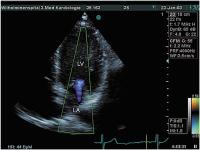

Mitralklappe

Abbildung 3: Apikaler Vierkammerblick, spätdiastolisch geschlossene Mitralklappe, keine Regurgitation bei 1:1-Leitung (LA = linker Vorhof, LV = linker Ventrikel)